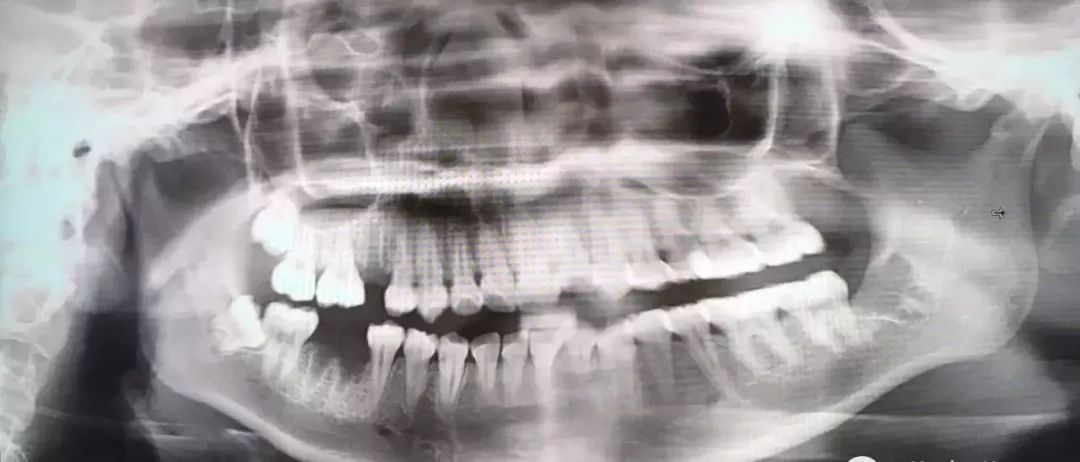

最后介绍一下,牙根弯曲,骑在下颌管上的智齿...由于下颌管内神经丰富,拔除的时候需要极度小心,而且看长相也知道这种模式的拔牙,非常难也非常贵!

也是先切开牙肉,翻开并露出骨头,切下牙冠后取出,再处理下面的牙根。

把牙根分成两半,根据牙根的走向,分别小心地撬出来,这个过程十分考验技术,要谨慎避免损伤到下颌神经...